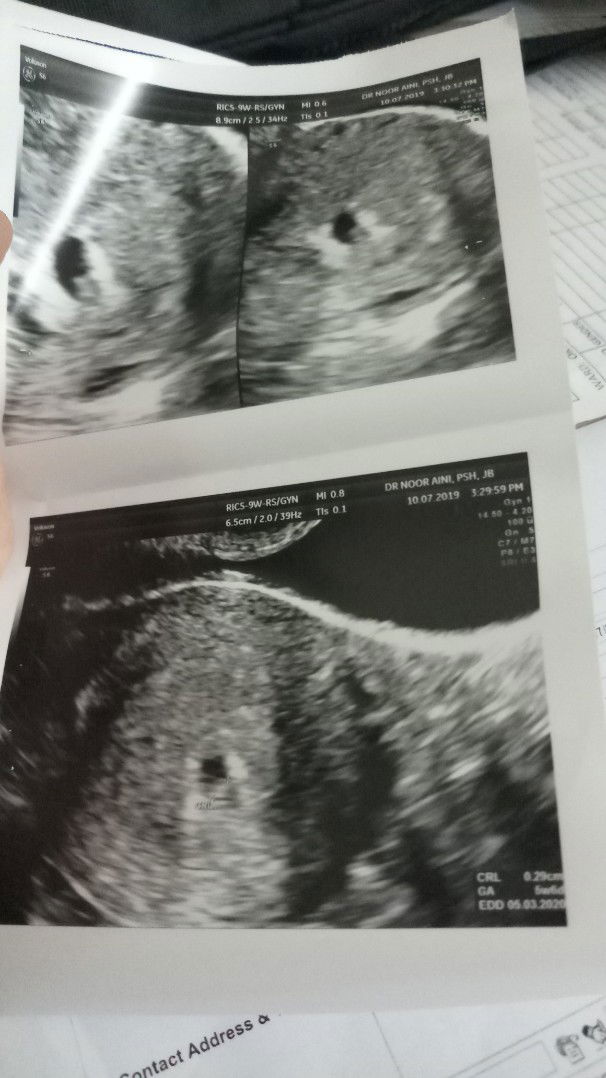

Assalamualaikum mommy2 semua. Saya last period 6/4 - 13/4 . Then bulan 5 lmbt 10hari , terus cek upt . Result samar2 . Tetibe esok nya bleeding byk . 15/5 - 28/5 baru stop sepenuhnya . Then xdtg period untuk June . 25/6 saya jumpa doc and buat darah Beta HCG . Result . 56.0 (3weeks) something . Next appt 2/7 repeat darah lagi and result 990 (4weeks) . Doc scan nmpk samar2 . Doc bg ubat utrogesran 100mg bd 1week. Next appt 10/7 . Today repeat darah result 5500. (5weeks). Doc scan nmpk kantung and dah ade heartbeat . Tapi doc ckp kantung xcantik . Do vaginascan and nmpk jelas heartbeat baby . So tadi doc bg mc untuk 2hari . Bg ubat sama untuk 2week . Injection hormon kuatkan rahim maybe . Next appt 24/7 . Ikut kiraan apps , 8weeks Ikut result darah , 7weeks Ikut scan 5weeks 2days Rasa down bila doc ckp kantung xcantik , tetibe bg mc , kat mc dia tulis 'treated misscariage' . Mommy2 . Thankyou baca luahan saya panjang2 . Doa kan baby saye selamat , sihat . Husband berharap sgt nak baby . InsyaAllah .